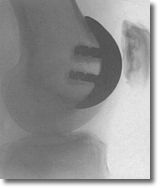

Custom Fit Patello-Femoral Replacement

Designed specifically for the small but challenging group of patients with isolated, end-stage patello-femoral disease.